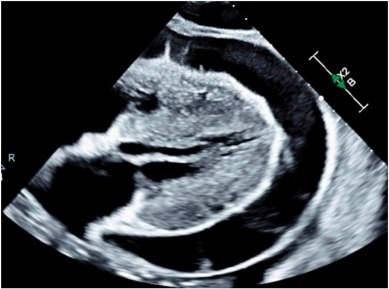

Our case in CRM:IC - patient in cardiac tamponade as the presenting sign of intolerance of a failed, non-functioning transplanted kidney. We describe a treatment escalation and ultimate resolution through transplant nephrectomy. doi.org/10.1016/j.crmi… [kwnsfk27.r.eu-west-1.awstrack.me]